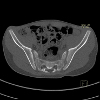

Рентгенография позвоночника (спондилография). Обследование костей и суставов позвоночника. Методика дает неврологу возможность получить подробную информацию о состоянии и строении позвонков, оценить расстояние между позвонками, изучить их отростки, межпозвоночные суставы и отверстия, определить подвижность отдельных сегментов позвонков, характер и степень кривизны. позвоночника. На рентгенограммах хрящевые структуры и спинной мозг почти не видны, но об их состоянии можно судить по некоторым косвенным признакам. Рентгенография позвоночника может быть обзорной или прицельной, нормальной или функциональной пробы.

Рентгенологическое исследование позвоночника в неврологии используется для определения причин неврологических нарушений при врожденных аномалиях, патологических изгибах и травматических повреждениях позвоночника. Методика предназначена для определения размеров позвоночного канала, выявления признаков опухолевых и воспалительных поражений спинного мозга, диагностики остеохондроза, выяснения степени выраженности дистрофических изменений дистрофии и определения причины недостаточности кровообращения в позвоночно-базилярном тазу головного мозга.

У пациентов с клиническими проявлениями остеохондроза рентгенография позволяет обнаружить смещение позвонков, деформацию их тел, уменьшение межпозвонковых расстояний, рост остеофитов, артроз межпозвонкового сустава, нестабильность и косвенные признаки наличия грыжи диска. На рентгеновском снимке вы не видите опухоли спинного мозга и самого спинного мозга, но вы можете судить о них по некоторым костным изменениям. Таким образом, разрушение тел позвонков указывает на наличие метастатической опухоли, расширение межпозвонкового отверстия - при невроме корешка позвоночника, локальное расширение позвоночного канала и разрушение дуг позвонка - в процессе экстрамедуллярной опухоли.

Обычно показания относятся к одной части позвоночника: шейному, грудному или пояснично-крестцовому. При определении показаний к рентгенографии в грудном и пояснично-крестцовом отделах врач учитывает, что процедура связана с облучением органов брюшной полости и таза. Несколько изображений этой зоны считаются нецелесообразными; при необходимости, повторные манипуляции рекомендуется, где это возможно, заменить другими исследованиями. Рентгенография не проводится во время беременности и при неспособности пациентки поддерживать неподвижность из-за неврологических или психических заболеваний. Седация может быть использована для обеспечения неподвижности пациента во время процедуры.

Обследование крестца, поясничного или крестцового отдела позвоночника требует подготовки больного. Это полное очищение кишечника, поскольку пузырьки газа и содержимое кишечника могут создавать тени, которые перекрывают основное изображение и усложняют диагностику. За несколько дней до манипуляций пациент должен воздерживаться от использования продуктов, способствующих образованию газов (белый хлеб, капуста, молочные продукты ;). Для очистки кишечника необходимо использовать ферменты и активированный уголь сегодня. Накануне опроса необходимо воздержаться от еды, чтобы сделать клизму.